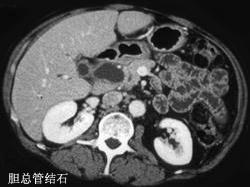

胆总管结石与胰头癌的主要鉴别特点是 ( )A、有无皮肤瘙痒B、有无肝功能改变C、有无淀粉酶改变D、有无肿大胆囊E、有无进行性黄疸

问题 胆总管结石与胰头癌的主要鉴别特点是 ( )

选项 A、有无皮肤瘙痒 B、有无肝功能改变 C、有无淀粉酶改变 D、有无肿大胆囊 E、有无进行性黄疸

答案 E